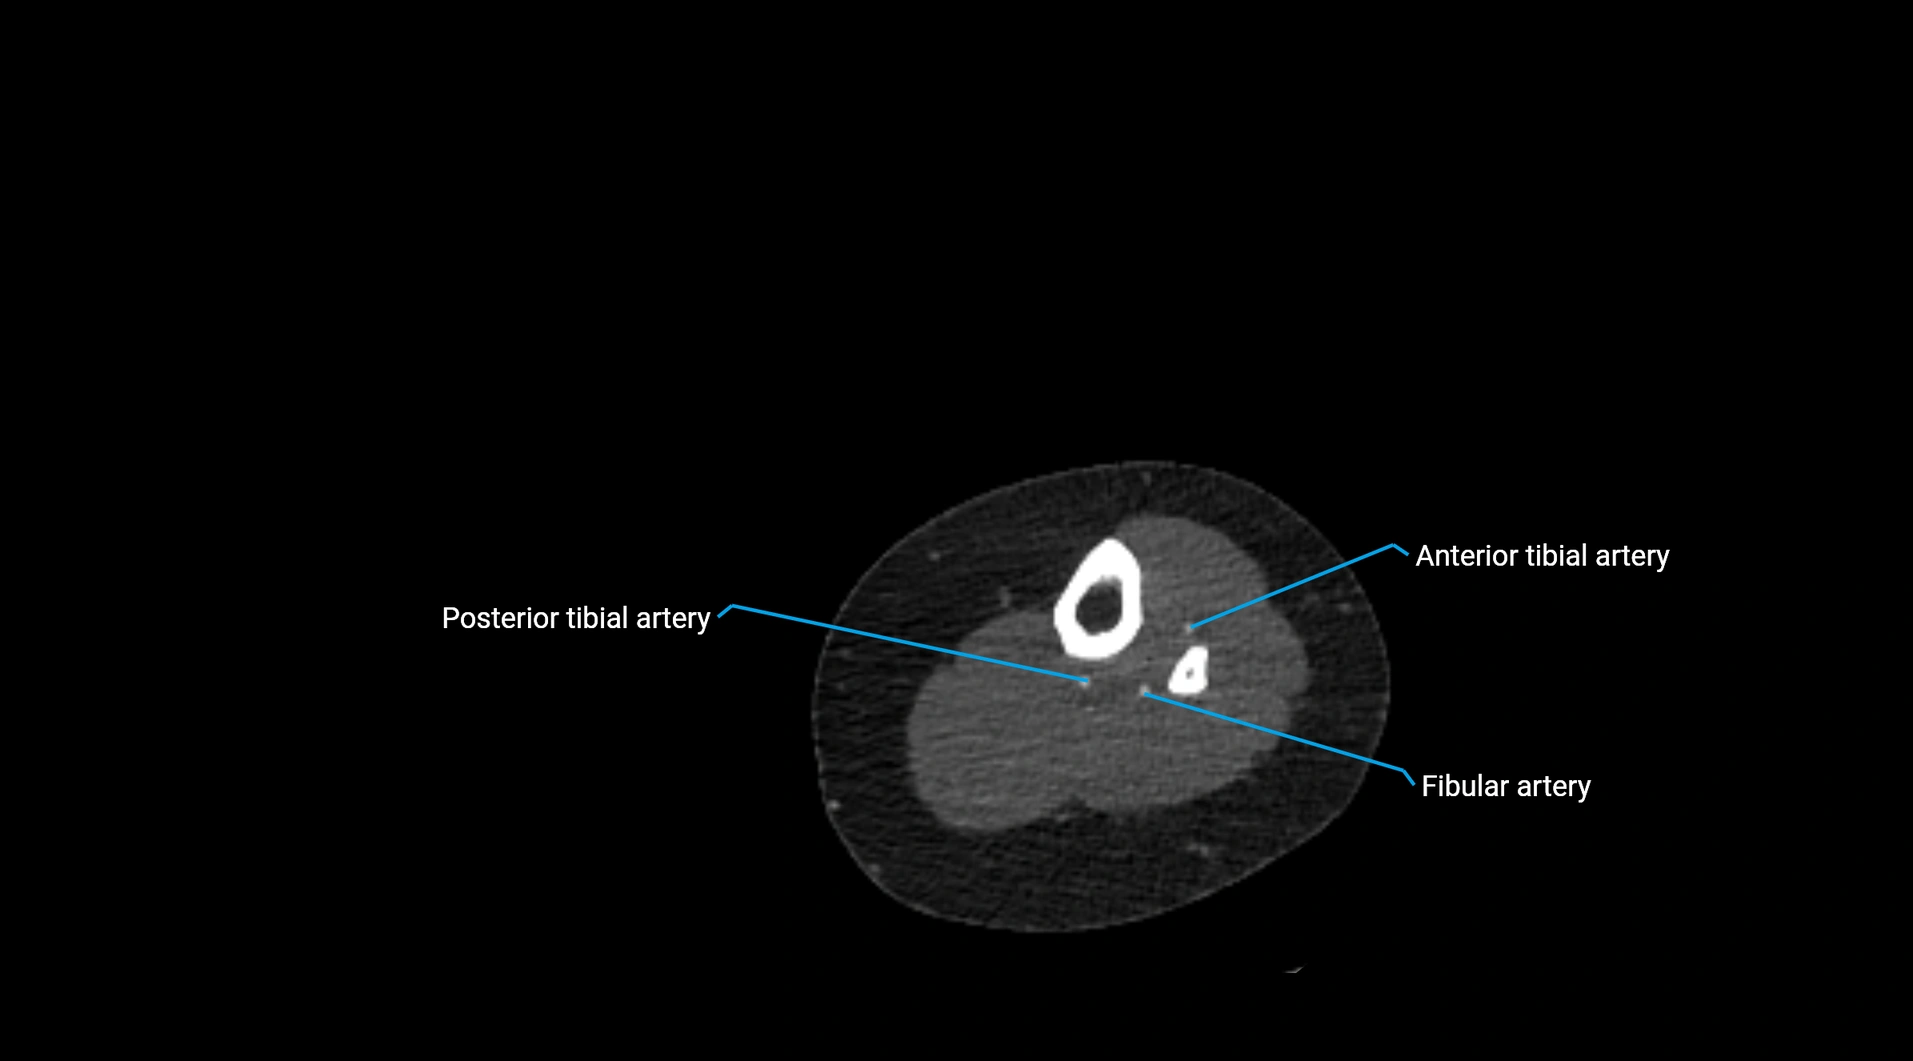

CT Appearance

Non-contrast CT:

• Appears as a tubular soft tissue structure anterior to vertebral bodies

• Calcified atherosclerotic plaques appear as hyperdense foci along the wall

• Useful for screening abdominal aortic aneurysm (AAA) size and mural calcification

Contrast-enhanced CT (CTA):

• Gold standard for abdominal aortic imaging

• Provides excellent detail of lumen, wall, aneurysm, thrombus, and branch vessels

• Multiplanar and 3D reconstructions help in aneurysm measurement, stent graft planning, and dissection evaluation

• Detects acute rupture, traumatic injury, or occlusion with high sensitivity